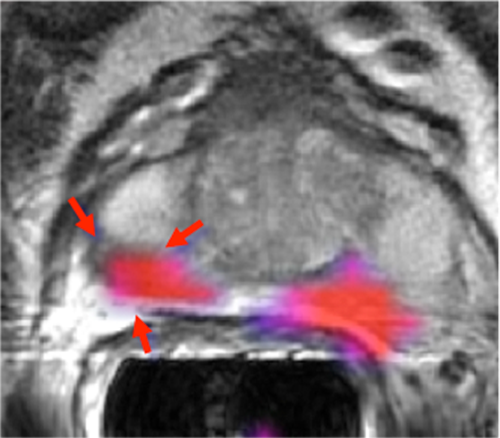

3D volumetric imaging with an optimized adiabatic fat suppression, combined with ARC or ASSET, provides high spatial and temporal resolution to capture contrast uptake patterns. The FSPGR Ax Dynamic image shows lesion characteristics generated using AW VS7's positive enhancement map. The T2 PROPELLER image demonstrates small FOV and motion-correction through the prostate.OrthoWorks